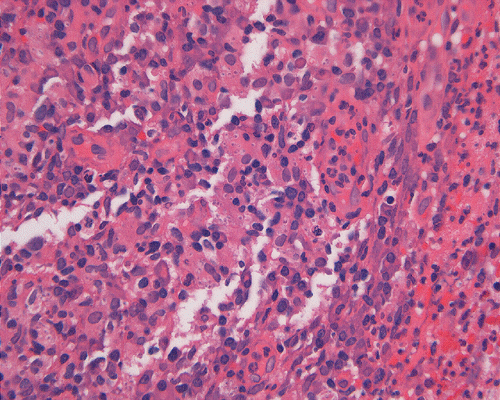

On low-magnification, the biopsy appears to be a piece of colonic mucosa without evidence of necrosis, erosion, or ulcer (Panel A). On medium-magnification, the lamina contains some vaguely formed collections of large cells (Ú in Panel B). On high-magnification, there are many large, round cells with eccentric nuclei. These are macrophages in clusters that are consistent with granulomas.  Many small, grayish to basophilic, vesicle-like structures are present in the cytoplasm (Panel in C). In other areas, these large, round cells do not really form small clusters and are admixed with lymphocytes (Panel D). Again, many small, grayish vesicle-like structures are present in these cells. A grayish to basophilic core is present and is surrounded by halo (Ú in Panel E).  These structures are most suggestive of microorganisms particularly fungus. On periodic acid Schiff (PAS), these vesicles appear bright purple-red (Panel F and G). The basophilic core is also strongly positive for PAS stain (Panel G). These microorganisms appear dark with Gomori methamine silver stain (Panel H and I).

In immunocomprised patients that have defective cellular immunity, granuloma formation may be rather indistinct as illustrated in our case. The yeast form of Histoplasma capsulatum is found in tissue and they are usually under 5 mm in diameter and appear as ovoid yeasts.  The lung is the most affected organ. Granuloma formation, typically multiple, with extensive caseous necrosis and a variable amount of calcifications are the typical pathologic changes in the lung. These granulomas are often demarcted from the surrounding tissue by a fibrous wall. Granulomas in the lung can get quite calcified with time. The pulmonary nodules can also enlarge slowly to give a wrongful clinical impression of neoplasm, the so-called histoplasmoma. The living yeast in tissue, often occur in clusters, has a basophilic center and a translucent halo that represents the capsule. They are often engulfed by histiocytes as illustrated in this case. Dead organisms appear eosinophilic and cannot be detected easily in granuloma by hematoxylinj-eosin stain. The microorganism is numerous and can be identified on routine hematoxylin-eosin stain with astute observation and high index of suspicion. Typically, there are numerous yeasts and they are present even in heavily calcified nodules or granulomas.